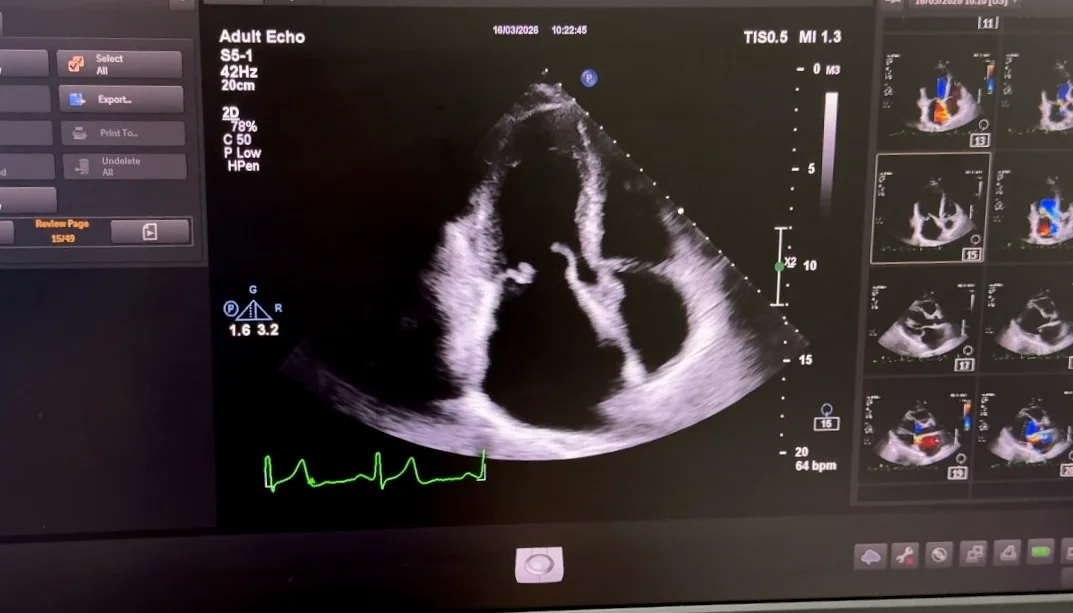

За даними ехокардіографії: виражений пролапс задньої стулки мітрального клапана та підозра на обрив хорд, що є причиною важкої мітральної недостатності (див. фото 1).